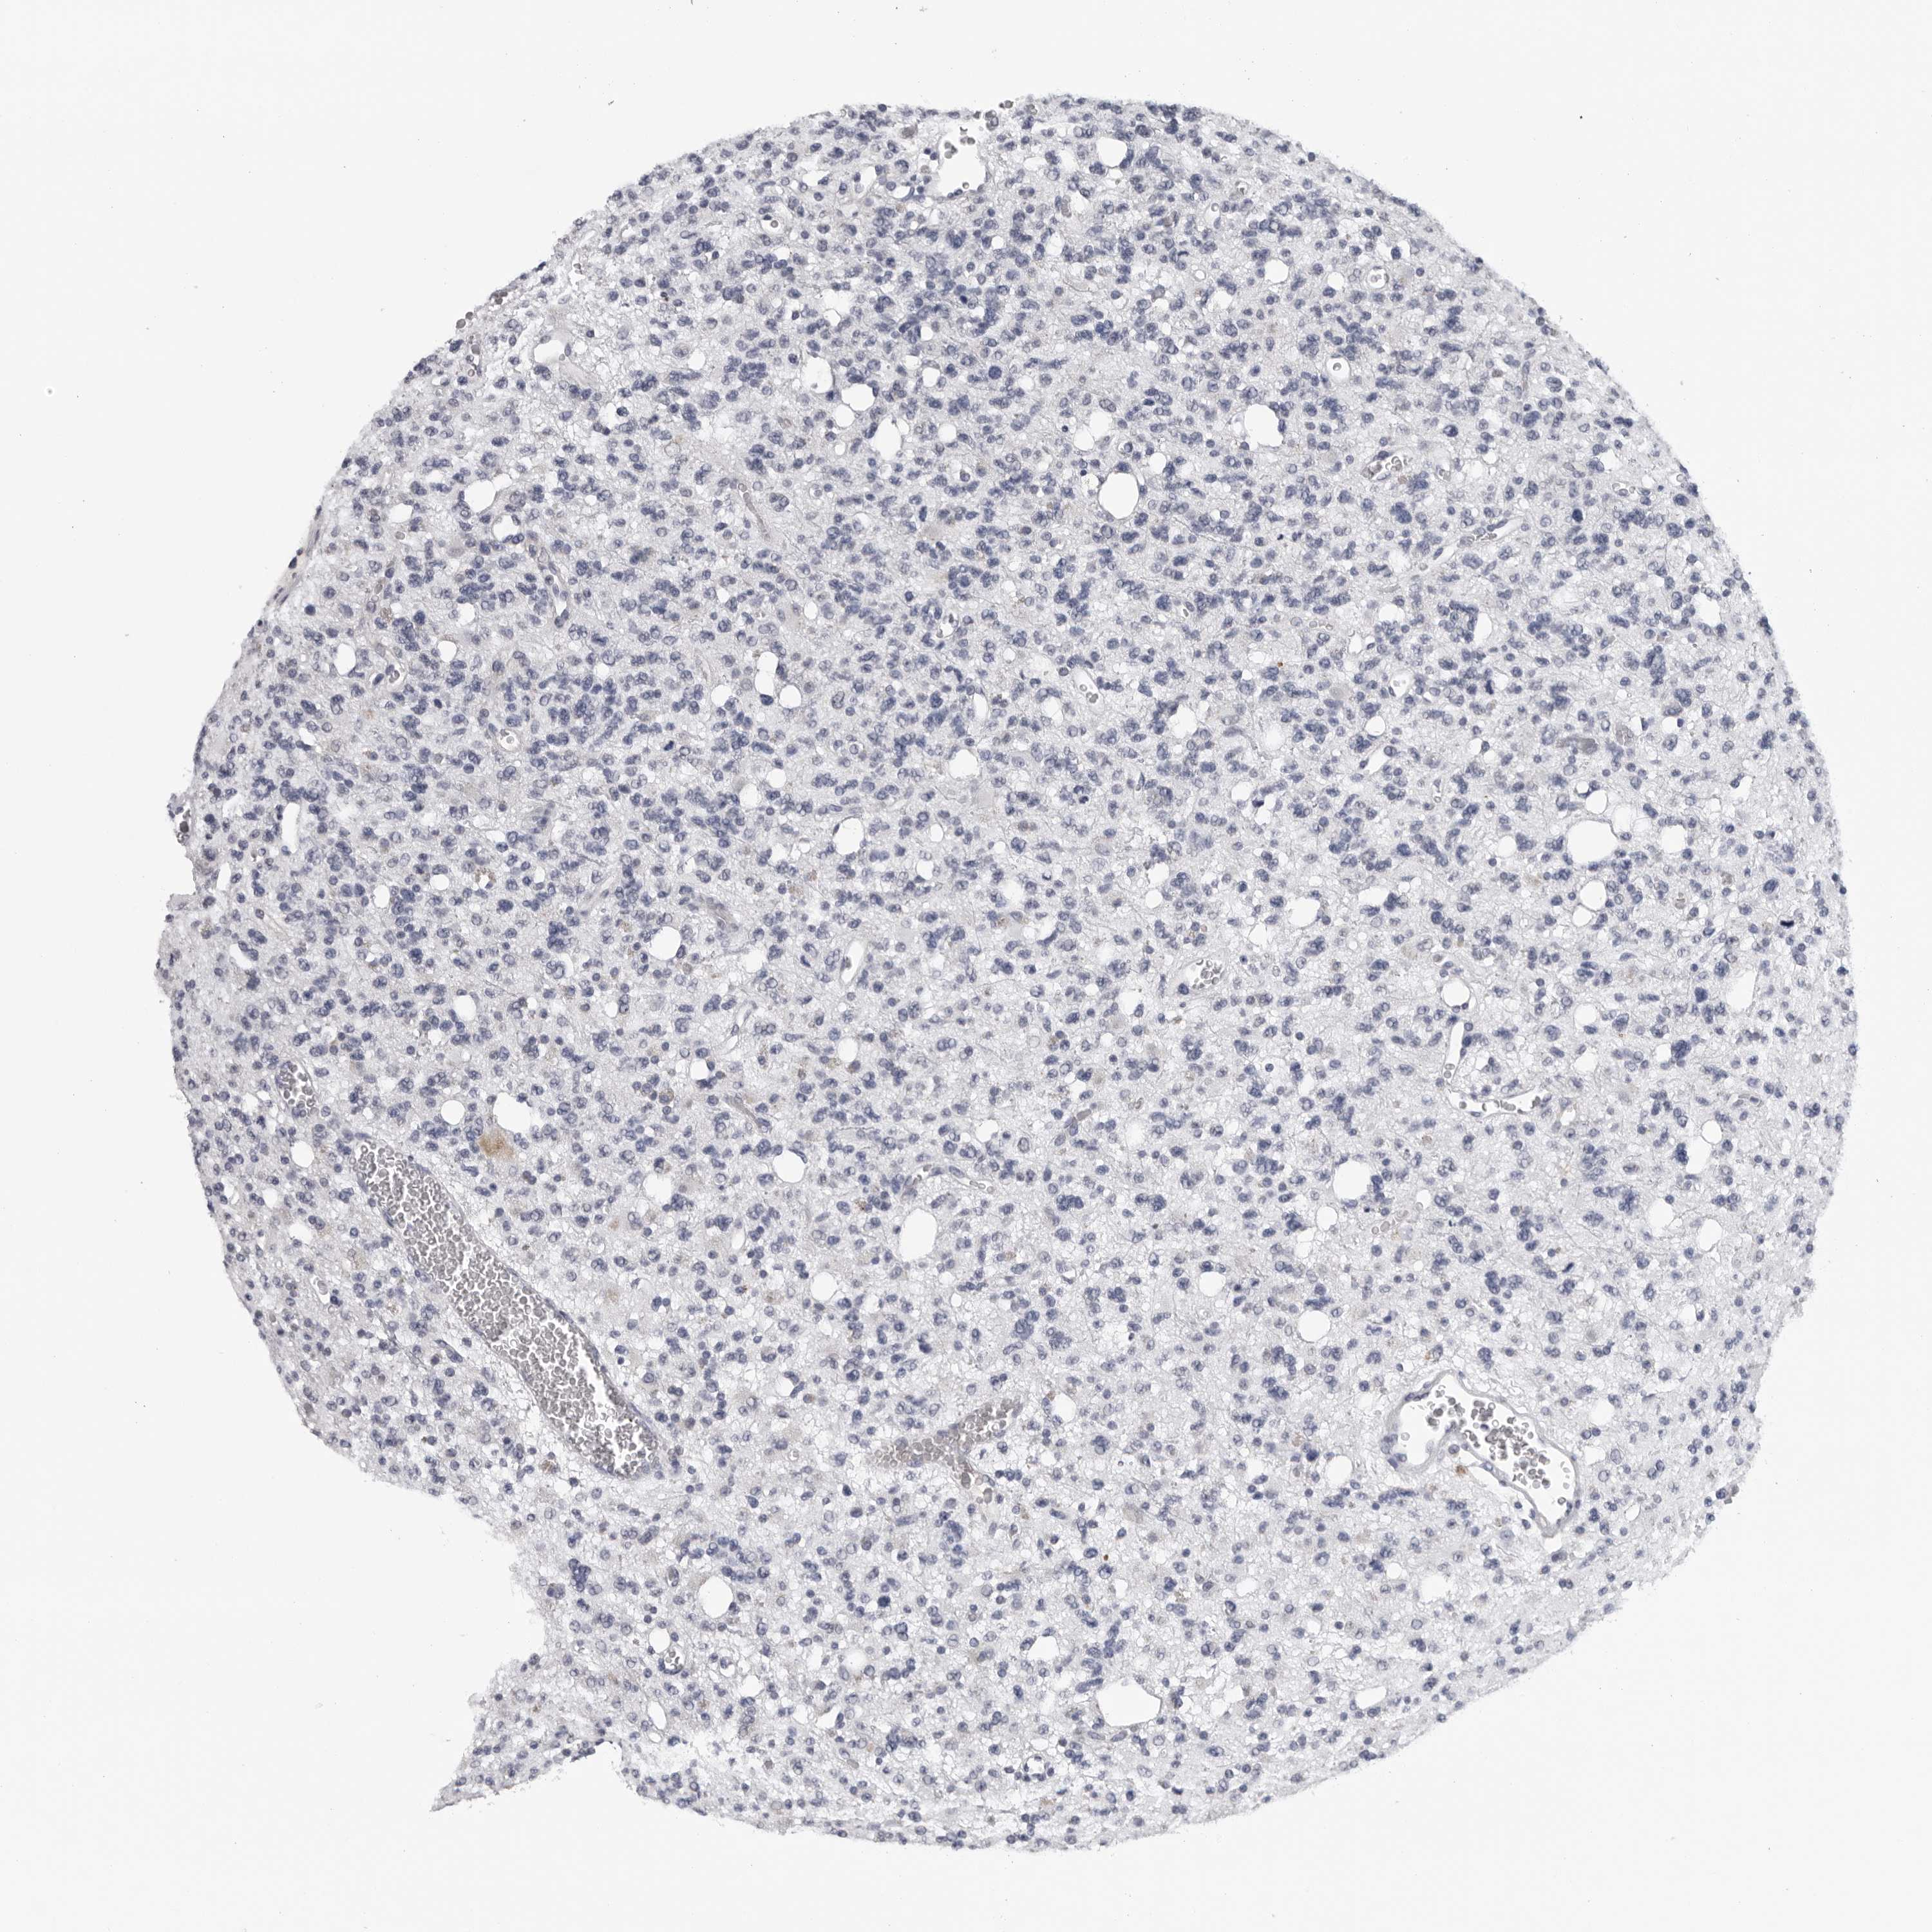

GLIOMA - Protein expressioni

A mouse-over function shows sample information and annotation data. Click on an image to view it in a full screen mode. Samples can be filtered based on level of antibody staining by selecting one or several of the following categories: high, medium, low and not detected. The assay and annotation is described here.

Note that samples used for immunohistochemistry by the Human Protein Atlas do not correspond to samples in the TCGA dataset.

Antibody stainingi

Antibody staining in the annotated cell types in the current human tissue is reported as not detected, low, medium, or high, based on conventional immunohistochemistry profiling in selected tissues. This score is based on the combination of the staining intensity and fraction of stained cells.

Each image is clickable and will lead to virtual microscopy that enables deeper exploration of all samples and also displays staining intensity scores, fraction scores and subcellular localization as well as patient and tissue information for each sample.

Antibody HPA024761

Antibody HPA029557

Staining

High

Medium

Low

Not detected

Intensity

Strong

Moderate

Weak

Negative

Quantity

>75%

75%-25%

<25%

None

Location

Nuclear

Cytoplasmic/membranous

Cytoplasmic/membranous,nuclear

Glioma, malignant, High grade

Glioma, malignant, Low grade

Glioblastoma, NOS